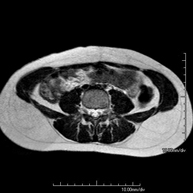

- Lumbar spine MRI

This non-invasive diagnostic procedure uses an electromagnetic field and radio waves (from a transmitter and receiver) to acquire high-definition anatomical images of the lumbar and sacral regions. It is a radiation-free procedure. Indicated for: trauma, sciatica, herniated discs, tumours, infections.

- Sacrum-coccyx MRI

This non-invasive diagnostic procedure uses an electromagnetic field and radio waves (from a transmitter and receiver) to acquire high-definition anatomical images of the sacrum and coccyx. It is a radiation-free procedure. Indicated for: sacrococcygeal pain, trauma.